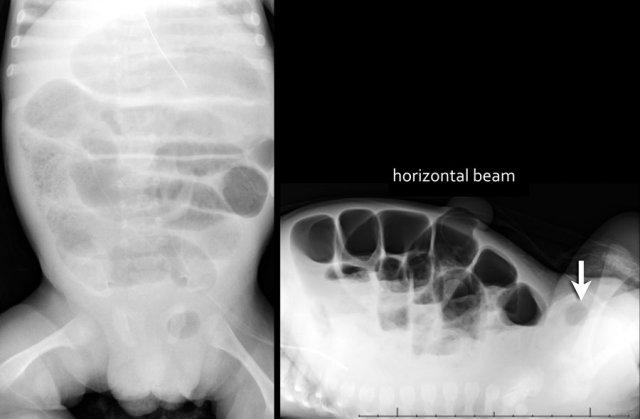

Trên hình ảnh bên trái, ruột bị giãn và đường kính vượt quá khoảng cách liên cuống L2 ở bệnh nhân tắc ruột phân su.

Trên hình ảnh bên phải, có hình ảnh giãn ruột mức độ nặng ở trẻ sơ sinh bị teo hỗng tràng.

Từ ba quai ruột non giãn trở xuống trên phim X-quang bụng thường gợi ý tắc ruột cao.

Hình ảnh bên trái minh họa một trường hợp teo hỗng tràng.

Nhiều hơn ba quai ruột giãn gợi ý tắc ruột thấp.

Hình ảnh bên phải là một trường hợp teo hồi tràng.